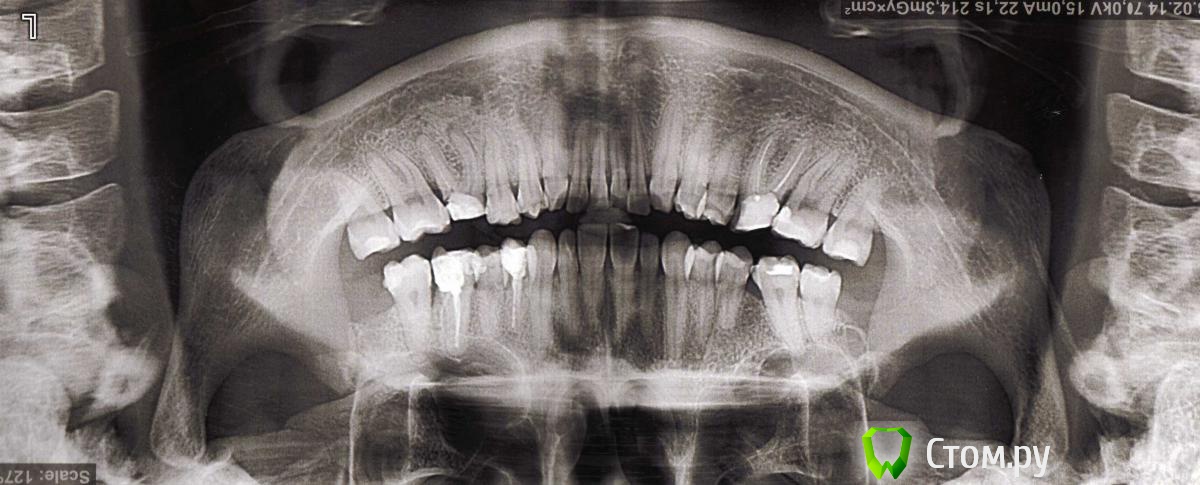

ОлиЯ Опубликовано 13 февраля, 2014 Автор Поделиться Опубликовано 13 февраля, 2014 это четверть данных(учитывая качестов снимка-1/10) теперь фото и ТРГ))доктор как вы сказали. все сделала))) Ссылка на комментарий

Ayrat_zub Опубликовано 13 февраля, 2014 Поделиться Опубликовано 13 февраля, 2014 (изменено) доктор как вы сказали. все сделала)))гораздо лучше))) оптг вверх ногами вопрос только как будут закрывать промежутки, , - 1- на верхней челюсти, там где нет 6-ки, 7-ка просто "наклонилась вперед", необходимо ее выровнять, и если не планируется имплантация 6-ки, то закрыть промежуток корпусно, сдвинув 7-ку 6-ку вперед,2-на нижней челюсти 6-ки правда с сомнительным прогнозом, терапевты лучше скажут, если их убирать без имплантации, то так же, нужно закрывать промежутки, корпусно двигая 7-ки и 8-ые зубы)скорее всего понадобиться немало времени+ жевательная поверхность 7-ок несколько различается от 6-ок, необходимо будет сделать реставрацию по окончании перемещения) детальнее план только с моделями и фото на очной консультации можно построить)верхняя 6-ка -тоже не очень, отпишитесь в раздел "терапии") Изменено 13 февраля, 2014 пользователем Ayrat_zub Ссылка на комментарий